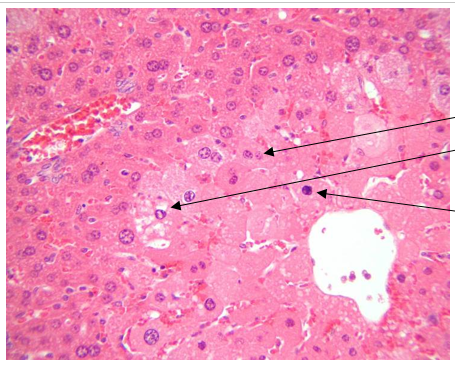

What organ are we in?

What term is appropriate for the process taking place in these cells?

The liver.

Coagulation necrosis

At the periphery of the centrilobular zones, there is a zone in which there are many enlarged hepatocytes with very pale, sometime granular cytoplasm and a perinuclear clear space.

What term is appropriate for these cells?

Acute cell swelling, or hydropic degeneration

What is the pathogenesis of coagulation necrosis?

For coagulation necrosis, when cell and organelle swelling progresses, further loss of ATP occurs, glycolysis ensues, loss of calcium regulation progresses, calcium enters the cell in large amounts resulting in phospholipases being activated (details for later), and the cell begins to die by necrosis.

What is the pathogenesis of acute cell swelling?

For acute cell swelling, metabolism of chloroform by the cytochrome P450 of the SER, especially in centrilobular hepatocytes, leads to production of metabolites (many free radicals) that cause lipid peroxidation of cell and organelle membranes. Damage to mitochondria leads to insufficient ATP production causing inadequate functioning of the Na-K pump, net influx of Na and therefore water, and cell swelling. Damage to the cell plasma membrane may lead to excess leakage and loss of volume control leading to cell swelling as sodium and water enter the cell in amounts exceeding the ability of the pumps to regulate.